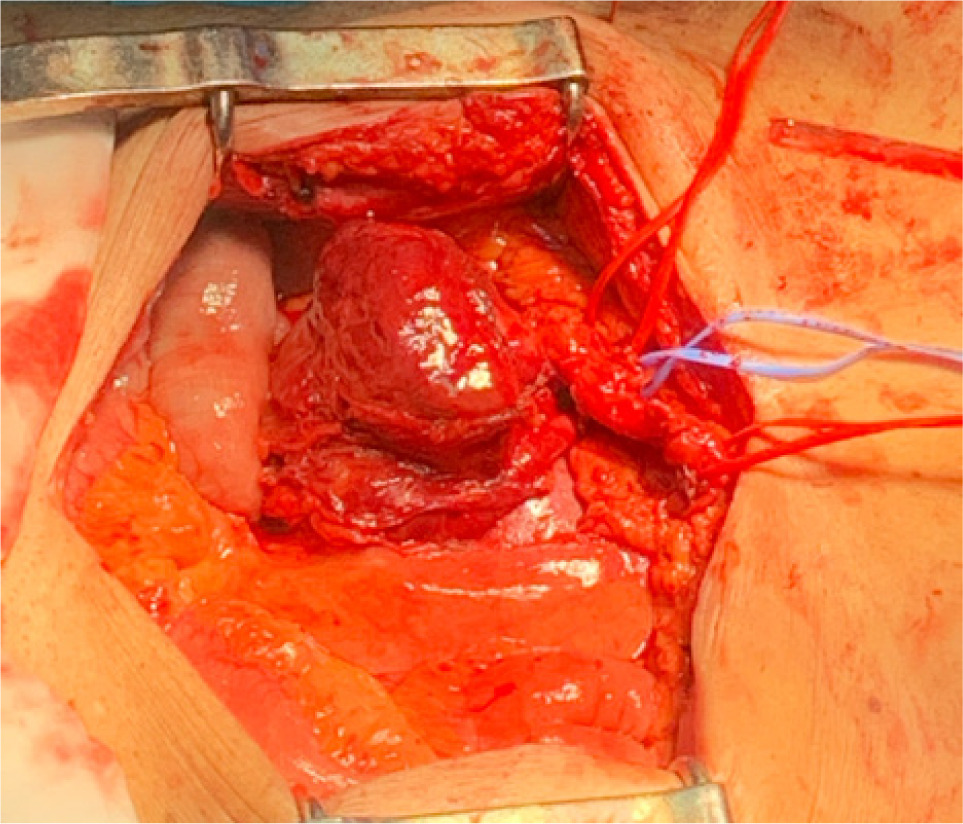

Bilateral RP and ureteric catheterization were first performed for the identification of the hila and calyces of the HSK (Figures 4 & 5). A lower midline laparotomy was performed. The tumor was identified, measuring 7 cm in diameter (Figure 6). Careful dissection of complex hilar structure was performed. Two renal arteries and two renal veins supplying the right side were identified and slung (Figure 7). The tumor was resected with artery clamping (Figure 8). The right lateral calyx of the pelvicalyceal (PC) system was involved and resected. The PC system was closed with 3/O PDS. Renorrhaphy was completed with 3/O V-Loc, and parenchyma was closed with 2/O V-Loc. Ischemic time was 20 minutes, and total operation time was 332 minutes. Blood loss was 420 mL. The patient had completed 1 week of levofloxacin and was discharged on postoperative day 6 with one kick of fever that spontaneously subsided.

Figure 7: Carefully slung vasculatures.